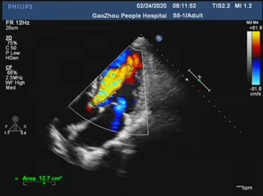

心脏彩超

主动脉瓣舒张期见中-大量红色返流,返流面积10.32cm2;

左室射血分数EF值:46%;

左室舒张末期内径(LVD):50 mm;

升主动脉增宽;

左房增大并左室增大,左室壁运动异常;

主动脉瓣评估:主动脉瓣重度关闭不全。

在多学科协作下,高州市人民医院心脏外科陈凯明、刘浪教授团队完成首例VitaFlow Liberty™主动脉瓣置换。经过2个小时紧张有序的操作,术中借助VitaFlow Liberty™的可回收技术,帮助瓣膜精准定位植入,术后造影检查和心脏彩超评估瓣膜形态活动良好,没有瓣周漏。手术取得圆满成功,患者心功能改善显著,次日转回普通病房。